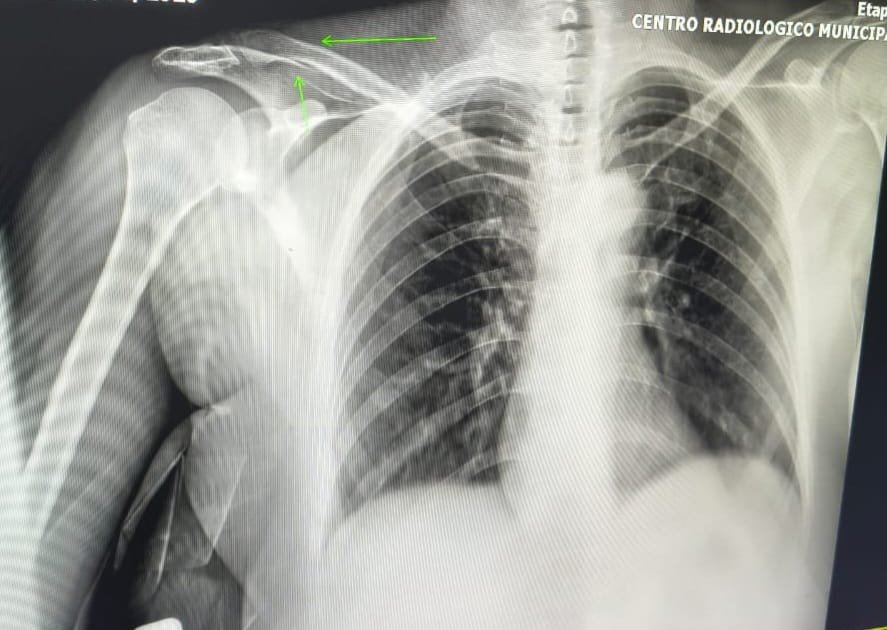

A mulher foi encaminhada inicialmente ao Hospital Municipal de Ibaté e, devido à gravidade dos ferimentos, precisou ser transferida para a UTI da Santa Casa de São Carlos. Conforme informado, ela sofreu fraturas na mandíbula, no nariz e na clavícula.